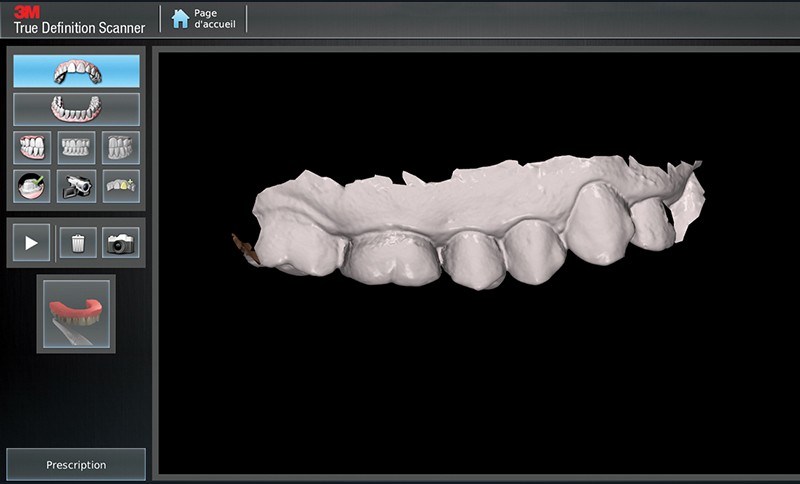

Cas clinique : Dr Arnaud Soenen